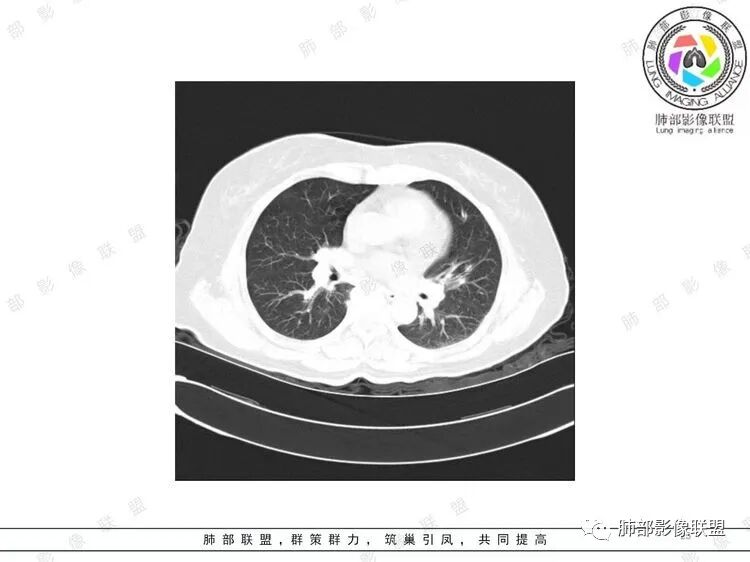

胸CT:双中下肺支气管壁明显增厚,双下肺胸膜下可见实变区。部分病变呈楔形影。

影像上:多发结节沿血管分布;双下叶支气管血管束简直增厚,偏血管,支气管通畅

首先肺部气道来源的病变不符合

因为支气管壁增厚,远端应该小气道病变,这个不是,反而是血管增粗明显

加上结节的分布,支持血管相关病变